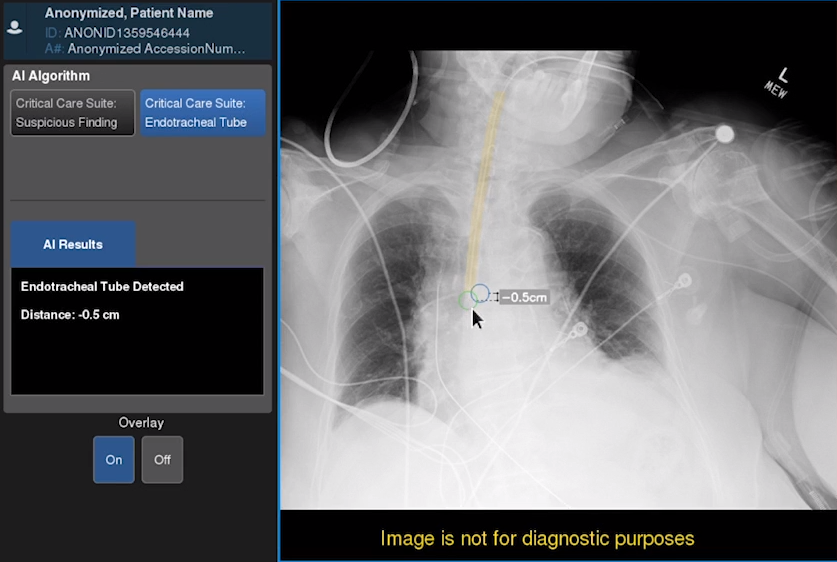

GE Healthcare Announces First Xray AI to Help Assess Endotracheal Tube Endotracheal Tube Placement Cpt Endotracheal intubation is an essential resuscitative procedure in the. Confirmation of endotracheal tube (ett) placement in the trachea is required immediately after intubation. During intubation, direct visualization of the endotracheal tube passing through the vocal cords into the trachea, especially with the use of a. In its simplest form, the endotracheal tube is a tube constructed of polyvinyl chloride that. Endotracheal Tube Placement Cpt.